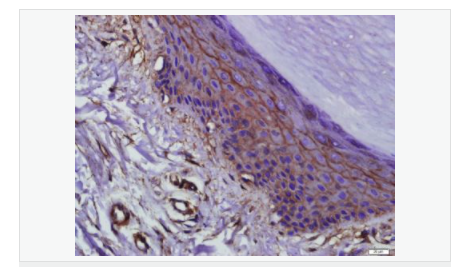

| 英文名稱 | Occludin |

| 中文名稱 | 緊密連接蛋白抗體 |

| 別 名 | Occludin, Occludin-1; Occludin1; Occludin 1; FLJ08163; BLCPMG; FLJ18079; FLJ77961; FLJ94056; MGC34277; Occludin; OCLN; OCLN_HUMAN; Tight junction protein occludin. |

| 產(chǎn)品應用 | WB=1:500-2000 ELISA=1:5000-10000 IHC-P=1:100-500 IHC-F=1:100-500 Flow-Cyt=1μg/Test ICC=1:100 IF=1:100-500 (石蠟切片需做抗原修復) not yet tested in other applications. optimal dilutions/concentrations should be determined by the end user. |

| 產(chǎn)品介紹 | This gene encodes an integral membrane protein which is located at tight junctions. This protein may be involved in the formation and maintenance of the tight junction. The possibility of several alternatively spliced products has been suggested but the full nature of these products has not been described. [provided by RefSeq]. Function: May play a role in the formation and regulation of the tight junction (TJ) paracellular permeability barrier. Subunit: Interacts with TJP1/ZO1 and with VAPA. Subcellular Location: Membrane; Multi-pass membrane protein. Cell junction, tight junction. Tissue Specificity: Localized at tight junctions of both epithelial and endothelial cells. Highly expressed in kidney. Not detected in testis. Post-translational modifications: Phosphorylated upon DNA damage, probably by ATM or ATR. Dephosphorylated by PTPRJ. May be phosphorylated by PKC during translocation to cell-cell contacts. Similarity: Belongs to the ELL/occludin family. Contains 1 MARVEL domain. SWISS: Q16625 Gene ID: 100506658 Database links: Entrez Gene: 18260 Mouse Entrez Gene: 100506658 Human Omim: 602876 Human SwissProt: Q16625 Human SwissProt: Q61146 Mouse Unigene: 592605 Human Unigene: 4807 Mouse Unigene: 31429 Rat Important Note: This product as supplied is intended for research use only, not for use in human, therapeutic or diagnostic applications. |